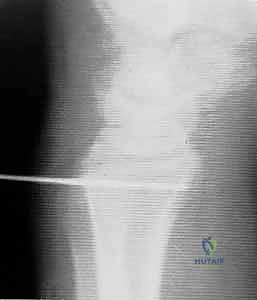

- Radial Tunnel Preparation:

- Using careful subperiosteal dissection, elevate the soft tissue from the dorsal edge of the sigmoid notch for several millimeters. This exposes the bone for tunnel placement.

- Identify the appropriate starting point for the radial tunnel: it should begin several millimeters proximal to the lunate fossa and approximately 5 mm radial to the articular surface of the sigmoid notch. This placement is crucial to avoid violating the articular cartilage and to ensure isometric graft placement.

- The tunnel should be oriented parallel to the articular surfaces of both the sigmoid notch and the lunate fossa.

- Drive a guidewire for a 3.5-mm cannulated drill bit from dorsal to volar through the radius, aiming for the volar aspect of the radius, distal to the pronator quadratus insertion.

- Fluoroscopy is mandatory here, fellows. Obtain both AP and lateral views to confirm precise guidewire placement, ensuring it's not too close to the articular surface and is exiting in a safe volar location.

* Once confirmed, use the 3.5-mm cannulated drill bit to create the radial tunnel. Irrigate to cool the bone.